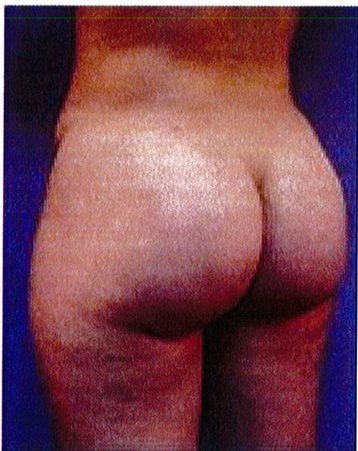

Hình. 19. . (A) Hình anh trước và (B) và sau phẫu thuật làm đầy mông của bệnh nhân chùng da vùng mông tương đối nhiều. Bệnh nhân được đặt khối implant dưới cân thể tích 330 mL ở hai bên.

Bệnh nhân 52 tuổi xuất hiện chùng da vùng mông (mức độ nặng), mong muốn giải quyết vấn đề này đồng thời tăng kích thước vòng ba. Hai khối anatomic implant

thể tích 330mL dạng silicone được đặt ở dưới cân cơ mông lớn.Hậu phẫu đánh giá thấy giảm thời gian hồi phục (Hình 19).